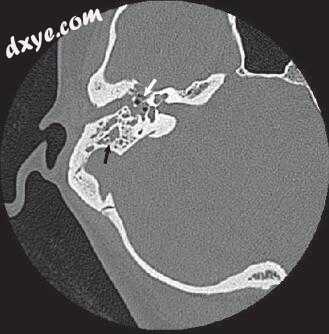

图-1. 颞骨骨扫描计算机断层扫描显示乳突的浑浊与保留骨隔。 注意皮质骨(白色箭头)和耳后肿胀和液体收集(黑色箭头)的缺陷。